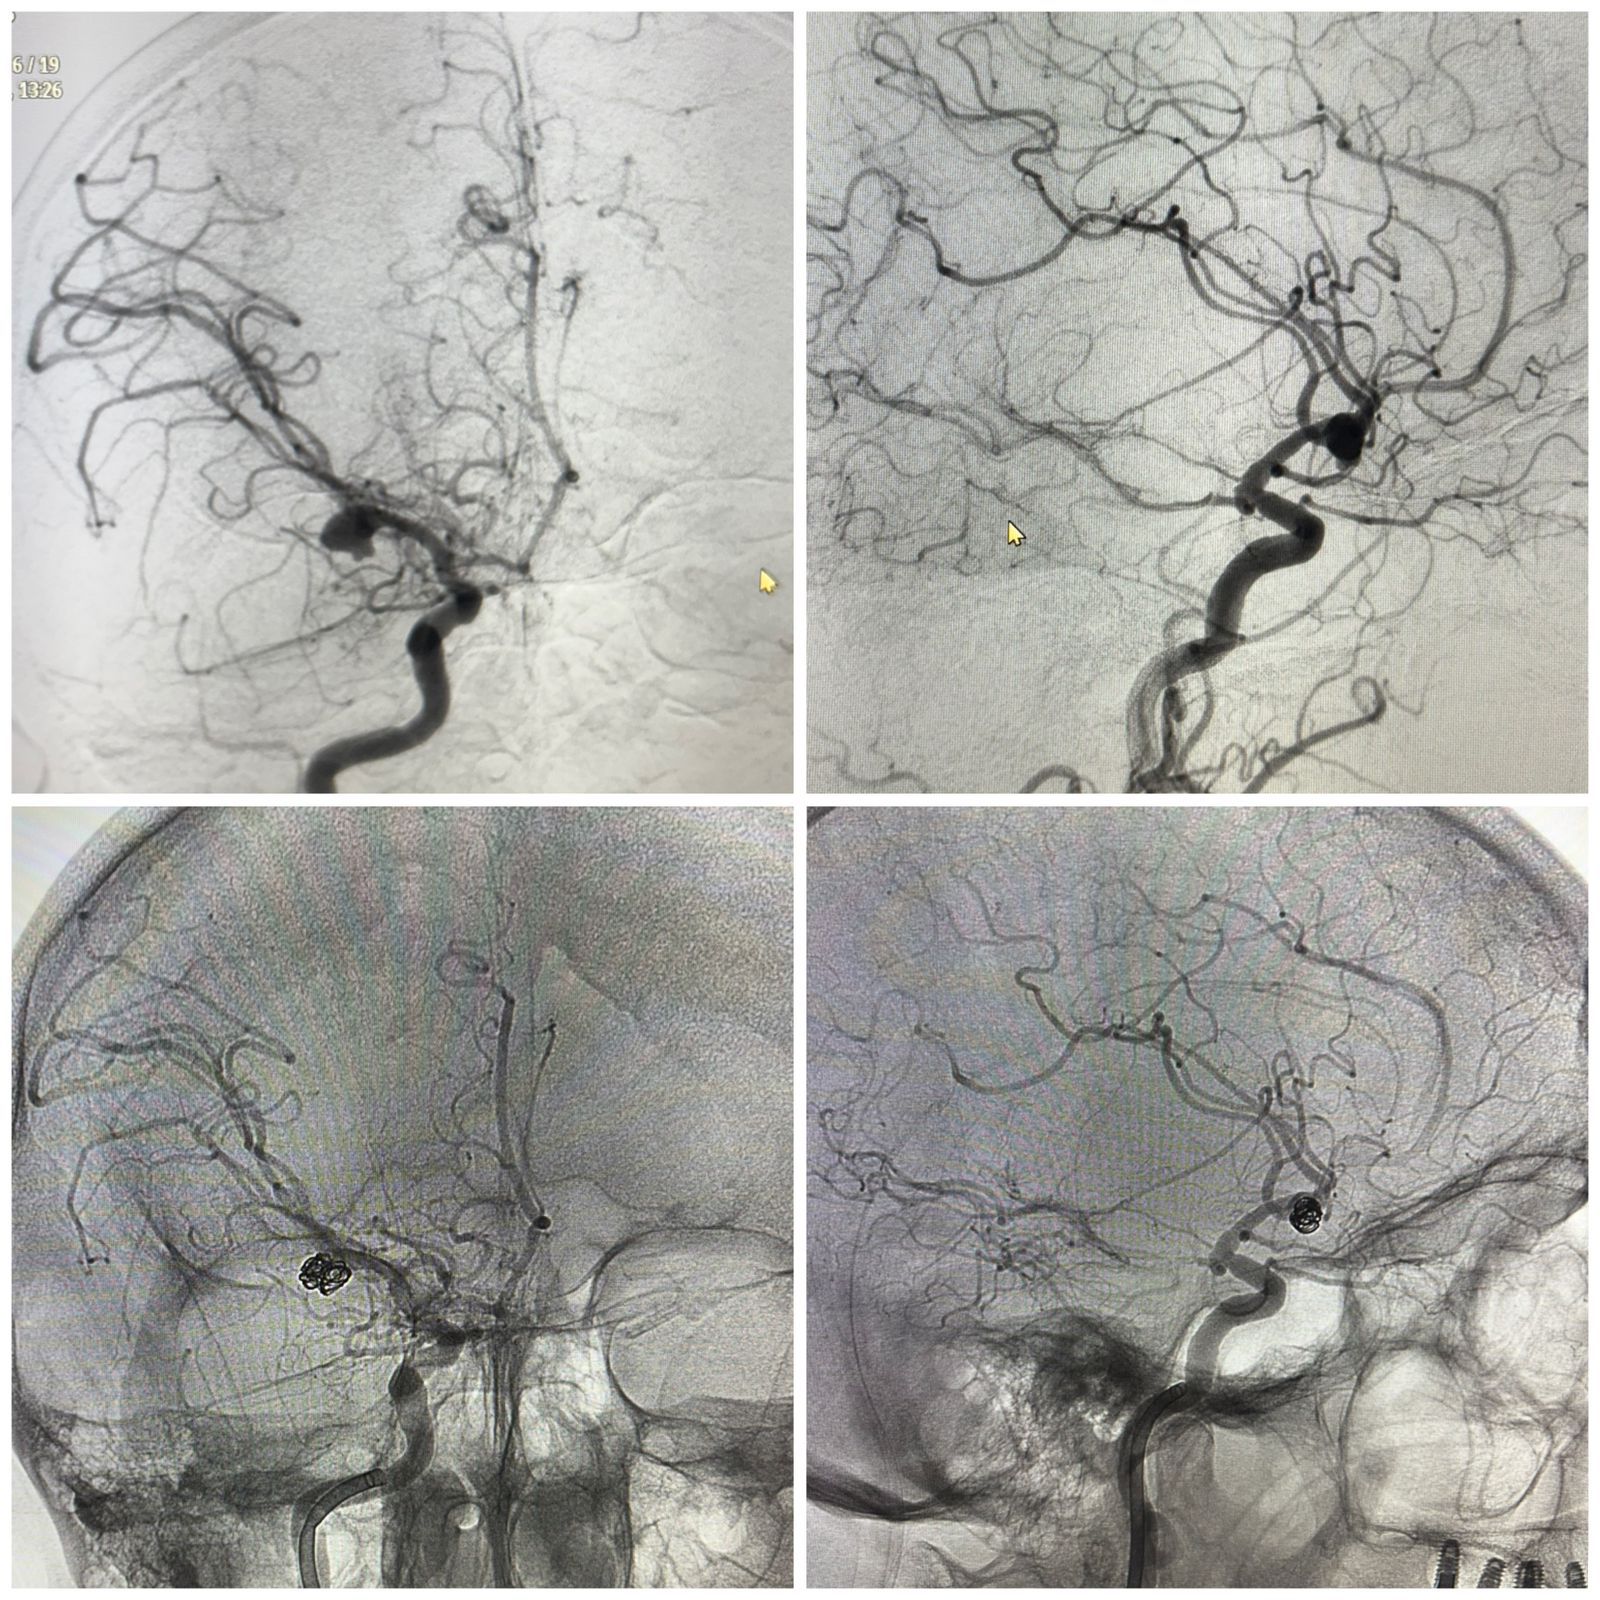

Мұндай оқиғалардың басым бөлігі науқас тіпті ауруханаға жетпей жатып, қайғылы аяқталады. Алайда бұл жолы әр минут шешуші рөл атқарған. Пациентті мультидисциплинарлық топ-невролог, реаниматолог, нейрохирургтер мен анестезиолог мамандар бірлесіп қабылдады. КТ-дан бастап ангиографияға дейінгі әрбір тексеру кезеңі бөлім меңгерушілері мен №4 ҚКА инсульт орталығы басшылығының қатысуымен өткен консилиумда талқыланып отырды.

«Ми құрылымдарының қысылу қаупі аса жоғары болғанын ескере отырып, пациентке үш отаны қатарынан жасау қажет болды. Біріншісі – жарылған аневризманы эндоваскулярлық эмболизациялау. Бұл – қанды тоқтатып, қайта жарылудың алдын алуға мүмкіндік беретін зақымы аз нейрохирургиялық әдіс. Екіншісі – сыртқы қарыншалық дренаж орнату. Оның мақсаты – басішілік қысымды төмендетіп, ми жұлыны сұйықтығының айналымын тұрақтандыру. Үшіншісі – ми ішіндегі гематоманы алып тастайтын декомпрессиялық ота. Бұл аса дәл микроскопиялық техниканы қажет ететін көлемді нейрохирургиялық араласу», дейді Алматы №4 қалалық клиникалық аурухана нейрохирургы Алдонгар Айсаутов.